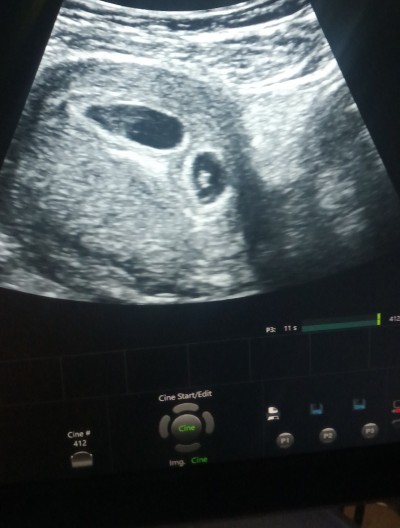

Suan 9.haftaya girdim doktora sordum tek yumurta ikizi mi yoksa çift yumurta ikizi mi diye tam emin birşey diyemedi ama çift yumurtaya benziyor dedi. Tabi en önemlisi sağlıklı ve hayırlı olmaları ama işte merak ediyorum acaba iki kız mı iki erkek mi yoksa bir kız bir erkek mi diye :) ilk hamileliğimde ikizdi erken doğum yapıp kaybettim onları o yüzden bunda çok korkuyorum sancılarımda çok oluyor hep peçeteyi kontrol ediyorum leke kanama gelmismi diye korkudan yani. Bide ikizlerde serklaj yaptıran var mı ileriki haftalarda doktora desem acaba her ihtimale karşı yapar mı tekrar erken doğum olmasın diye.

Çift yumurta kuzum baksana iki ayrı kese var

Evet iki ayrı gibi görünüyorda doktor tam belli değil çifte benziyor dedi o yüzden hani dedim bir sorayım canim

Çift yumurta gibiler canım .Ama ince noktaları var tabi doktor daha iyi bilir.Benimde ikizlerim var ayrı kese, ayrı plesantadadan besleniyorlardı.Rabbim sağlıkla kucagina almayı nasip etsin inşallah

Ücüz olabilir gibime de geliyor :)) büyük olan kesede sanki iki embriyo var gibi diğerinde tek hayırlısı olsun